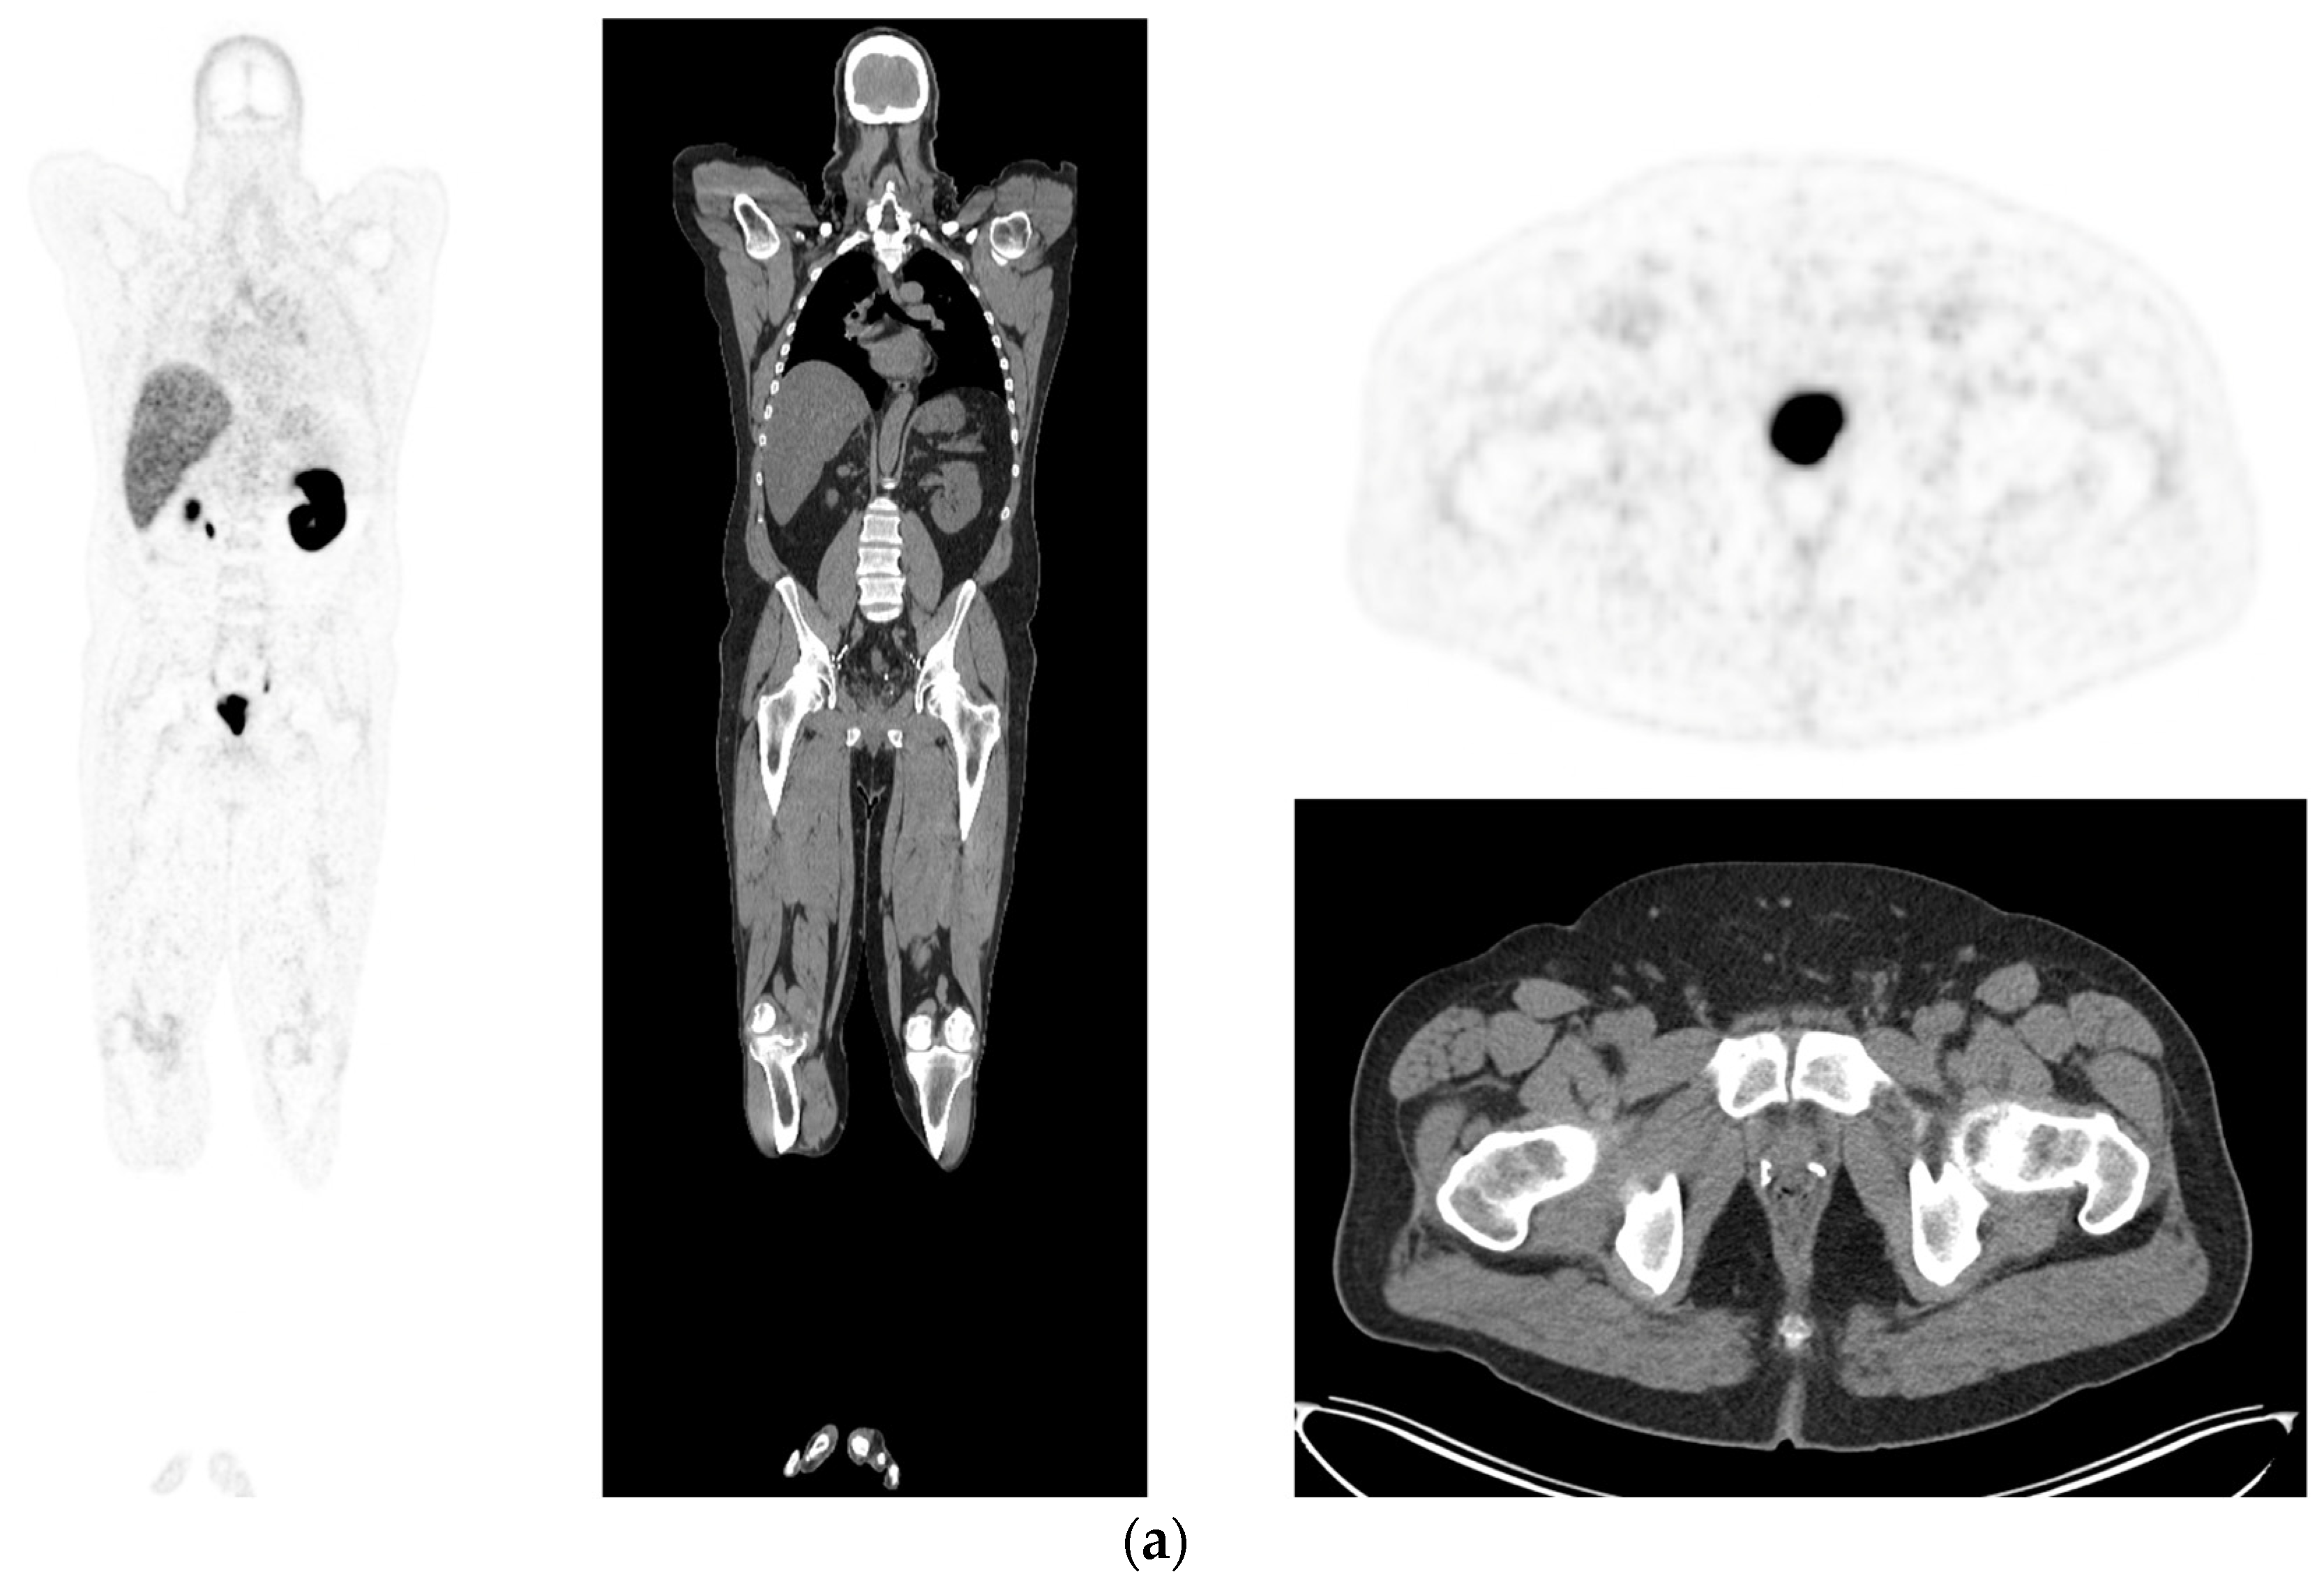

- McEwan, L.M.; Wong, D.; Yaxley, J. Flourodeoxyglucose positron emission tomography scan may be helpful in the case of ductal variant prostate cancer when prostate specific membrane antigen ligand positron emission tomography scan is negative. J. Med. Imaging Radiat. Oncol. 2017, 61, 503–505. [Google Scholar] [CrossRef]